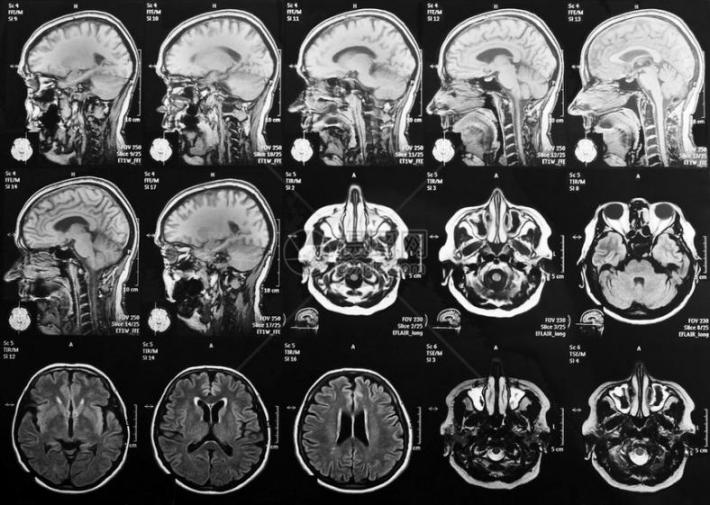

磁共振成像(MRI)就像是一种用强磁场给大脑照片的技术。人体内富含氢原子,这些氢原子在强磁场里会排好队,像小磁铁一样。这时,机器会发射出一种特殊的信号,短暂地“推”或“打扰”一下这些小磁针,让它们的队形暂时乱了。等这个“信号”停止后,被推乱的小磁针又会努力转回原来的方向。就在它们转回去的过程中,自己也会发出微弱的信号。机器捕捉到这些返回的信号,经过处理,就变成了我们看到的大脑清晰图像。

磁共振设备